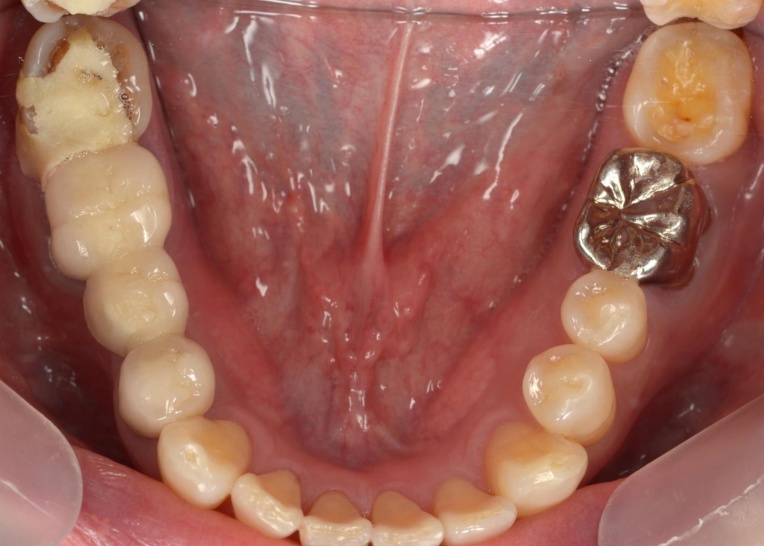

治療前

治療中

拝見したところ、右下奥歯(第2大臼歯)が折れていることが確認できました。

また、患者様は下顎が上顎よりも前に出る「反対咬合(こうごう)」、いわゆる受け口の傾向があることがわかりました。

折れている歯を一時的に利用しながら、受け口傾向にある噛み合わせが改善するよう、歯の位置を少しずつ調整していきました。